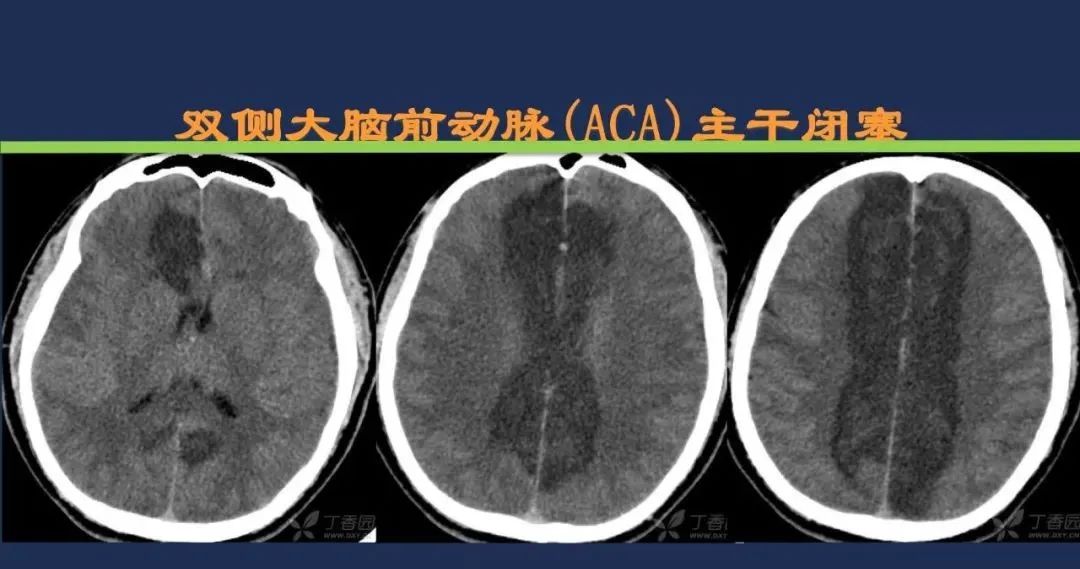

大脑前动脉